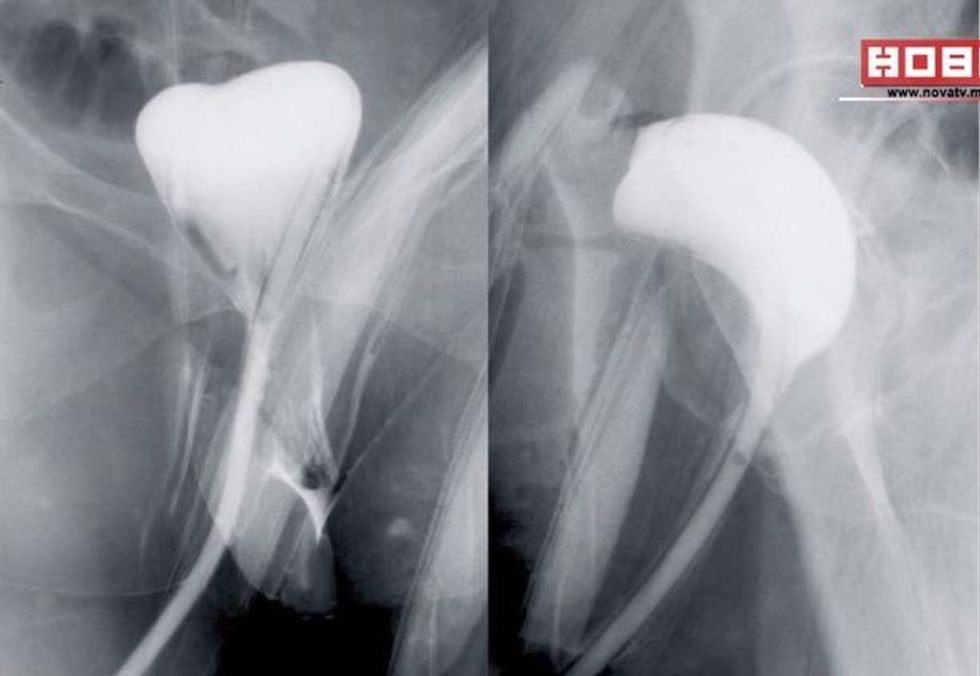

Jasminka Vellkoska vazhdon të paguaj çmimin e gabimit mjekësor. Ajo flet pas tre vitesh për herë të parë për rastin e saj kur mjekët ia ngjitën gabimisht vagjinën me zorën e trashë gjatë një operacionit për largimin e kancerit në abdomen, përcjell Telegrafi Maqedoni.

Dailymail.co.uk shkruan ''E mbijetuara nga kanceri i nxjerr gazrat nga vagjina pasi mjekët gabimish ia kanë ngjitur atë me zorën e trashë''Rastin e kanë komentuar edhe disa ekspertë të kirurgjisë që kanë edhe blogjet e tyre, duke e klasifikuar si marrëzi dhe pa kujdes që bie ndesh me principet e profesionit.